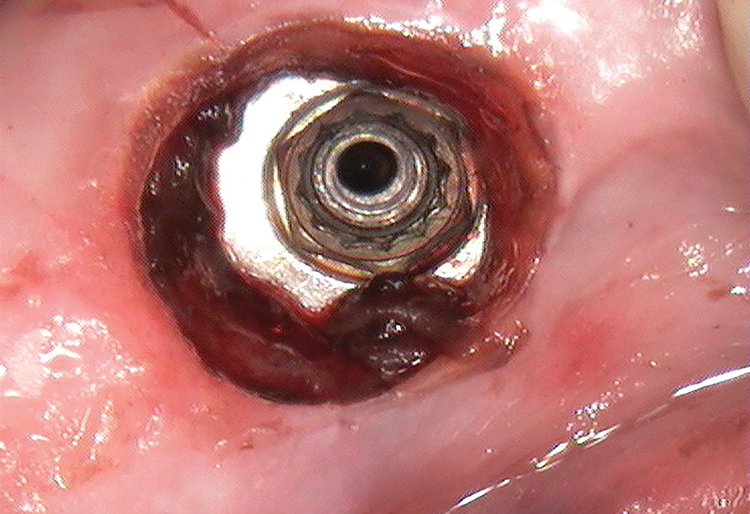

(6.) An ultrasonic tip with irrigation for brief intervals and a 25-gauge metal cannula were alternately used in a counterclockwise motion to reverse the screw fragment out to the first threads.

Figure 6

After the soak was complete, an ultrasonic tip was used with copious irrigation in a counterclockwise motion in short intervals to further loosen the screw fragment. The short intervals helped to reduce the amount of heat produced while still providing efficacy. After several rounds with the ultrasonic tip, a 25-gauge metal cannula was used to engage the top of the screw fragment and help rotate it in a counterclockwise direction. This use of the cannula was alternated with the ultrasonic tip to gain adequate movement of the fragment (Figure 6). Once the screw fragment was able to be retrieved, it was removed with the narrow suction tip (Figure 7). A healing abutment was then placed to contour the tissue until adequate healing occurred.